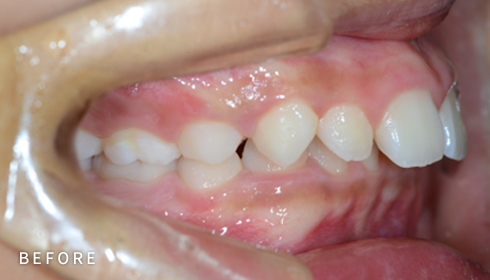

비발치 덧니 교정

덧니고민, 비발치로 교정하세요

악궁 확장, 미니 스크류, 치간 삭제 등 다양한 방법을 활용해 가능한 한

발치를 피하고, 자연스럽고 만족스러운 결과를 얻을 수 있도록

정밀하게 계획하고 진료합니다. 발치 여부가 애매한 경우,

‘레벨링 후 재평가’ 과정을 거쳐 비발치를 우선 고려합니다.